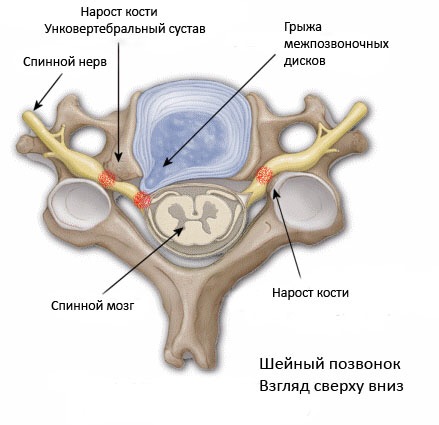

Остеоартрит фасеточных суставов: медицинские снимки и схемы